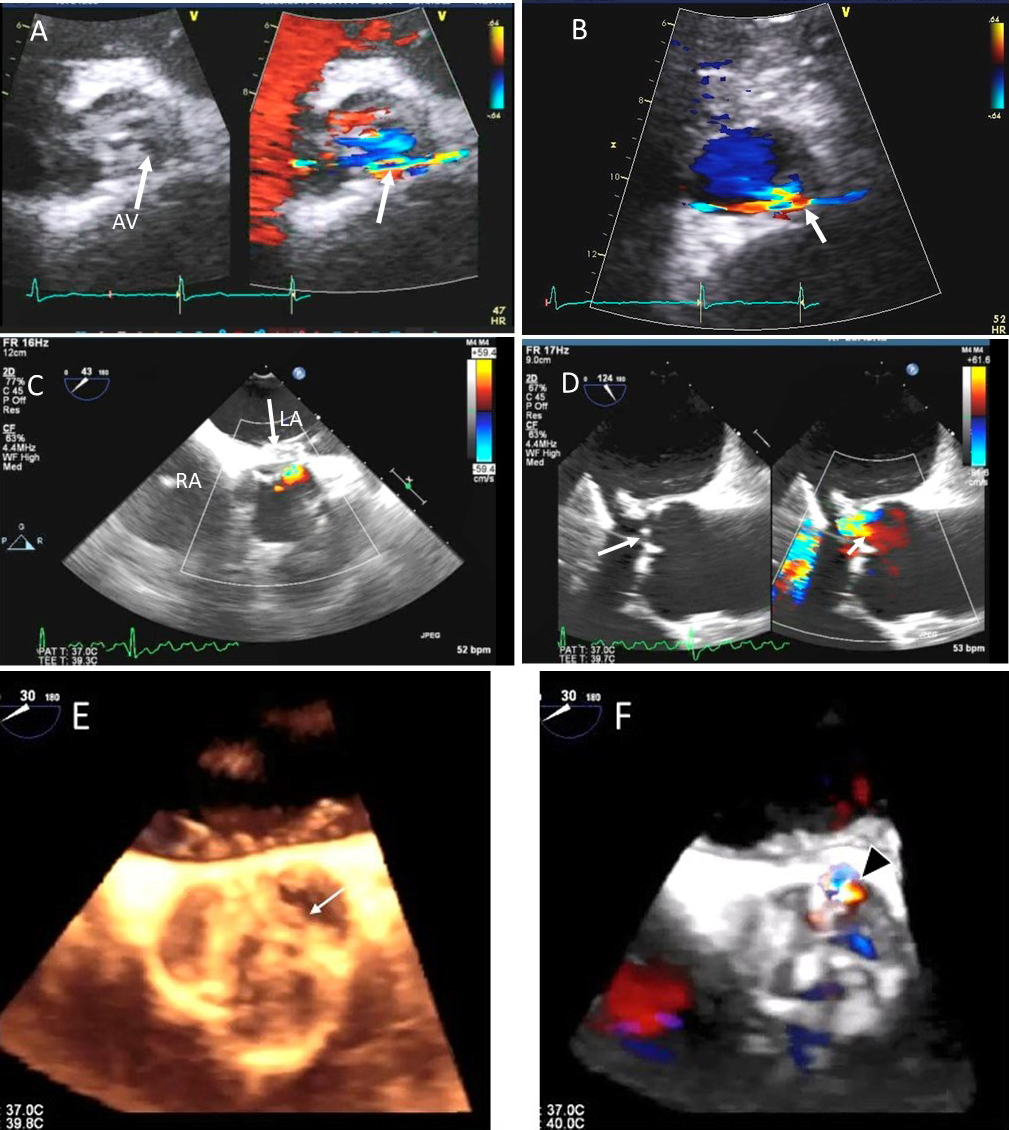

Fig. 8.Aortic regurgitation and left coronary cusp perforation. (A) TTE color Doppler parasternal short axis view demonstrating left coronary cusp perforation (white arrows), resulting in aortic regurgitation. (B) TTE color Doppler short axis view showing origin of aortic regurgitation through the left coronary cusp perforation (white arrow). (C) TEE color Doppler short axis view showing a better delineation of the origin of aortic regurgitation jet through the left coronary cusp perforation (white arrow). (D) TEE long axis view demonstrating the perforated coronary cusp on 2D (white arrow) with aortic regurgitation jet originating through the perforation (white arrow) and not through the aortic leaflet coaptation. (E) 3-dimensional (3D) TEE short axis view of the aortic valve showed a clear definition of the left coronary cusp perforation (white arrow). (F) 3-D TEE color Doppler short axis view showing aortic regurgitation jet originating through the left coronary cusp (black arrowhead). Direct planimetry of color Doppler aortic regurgitant orifice can be performed online or via offline post processing of 3D data sets without geometrical assumptions of PISA method or continuity equation.